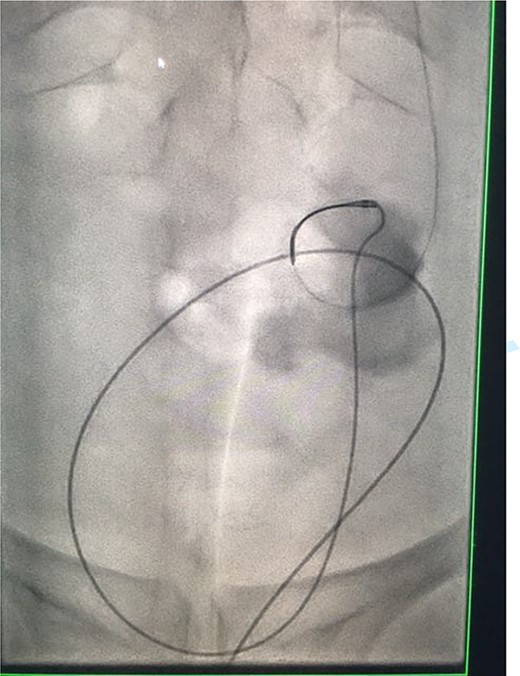

Under conscious sedation, using the previously inserted right percutaneous nephrostomy, antegrade access was achieved into the intrarenal collecting system and then into the proximal ureter. An 8 Fr × 11-cm access sheath was introduced. A guidewire was advanced antegradely through the site of ureteric transection and coiled in a position adjacent to the position of the guidewire that had been inserted retrogradely. A Gooseneck snare catheter was then passed over the guidewire and the snare was inserted (Figs 4 and 5). Under fluoroscopic guidance, the retrograde wire was retrieved and brought externally via the nephrostomy site, achieving through-and-through wire access (Figs 6 and 7).

Fluoroscopic images showing the antegrade Amplatz gooseneck snare catheter attempting to grasp the retrograde wire.